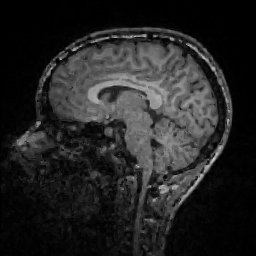

Improving image reconstruction from a sparse set of known pixels was the main motivation behind our work. Therefore, we applied it to two well-known natural images, lena and peppers, as well as to a medical image, a slice of a weighted brain MR scan (t1slice). For lena, we kept a random subset of only of the pixels. Due to the lower resolution of the peppers and t1slice images, we kept and , respectively.

Results for lena are shown in Figure 2, for peppers in Figure 3, and for t1slice in Figure 4. A quantitative evaluation in terms of MSE and AAE is presented in Table 4.1. In terms of the numerical results, our proposed method produced a more accurate reconstruction than any of the competing approaches. Visually, there is a clear difference between second-order (EED) and fourth-order approaches (Li1, Li2, FOEED). Especially, we found that the shapes of edges were reconstructed more accurately. For example, we noticed this around the shoulder and hat in the lena image (Figure 2). Similarly, the white and grey matter boundaries were better separated in the t1slice (Figure 4).

| t1-slice | MSE | 166.356 | 150.002 | 152.698 | 155.955 |

| AAE | 5.895 | 5.698 | 5.789 | 5.853 |

| t1-slice | MSE | 114.845 | 107.323 | 24.74 (FOEED) |

| AAE | 4.610 | 4.553 | 10.64 (EED) |